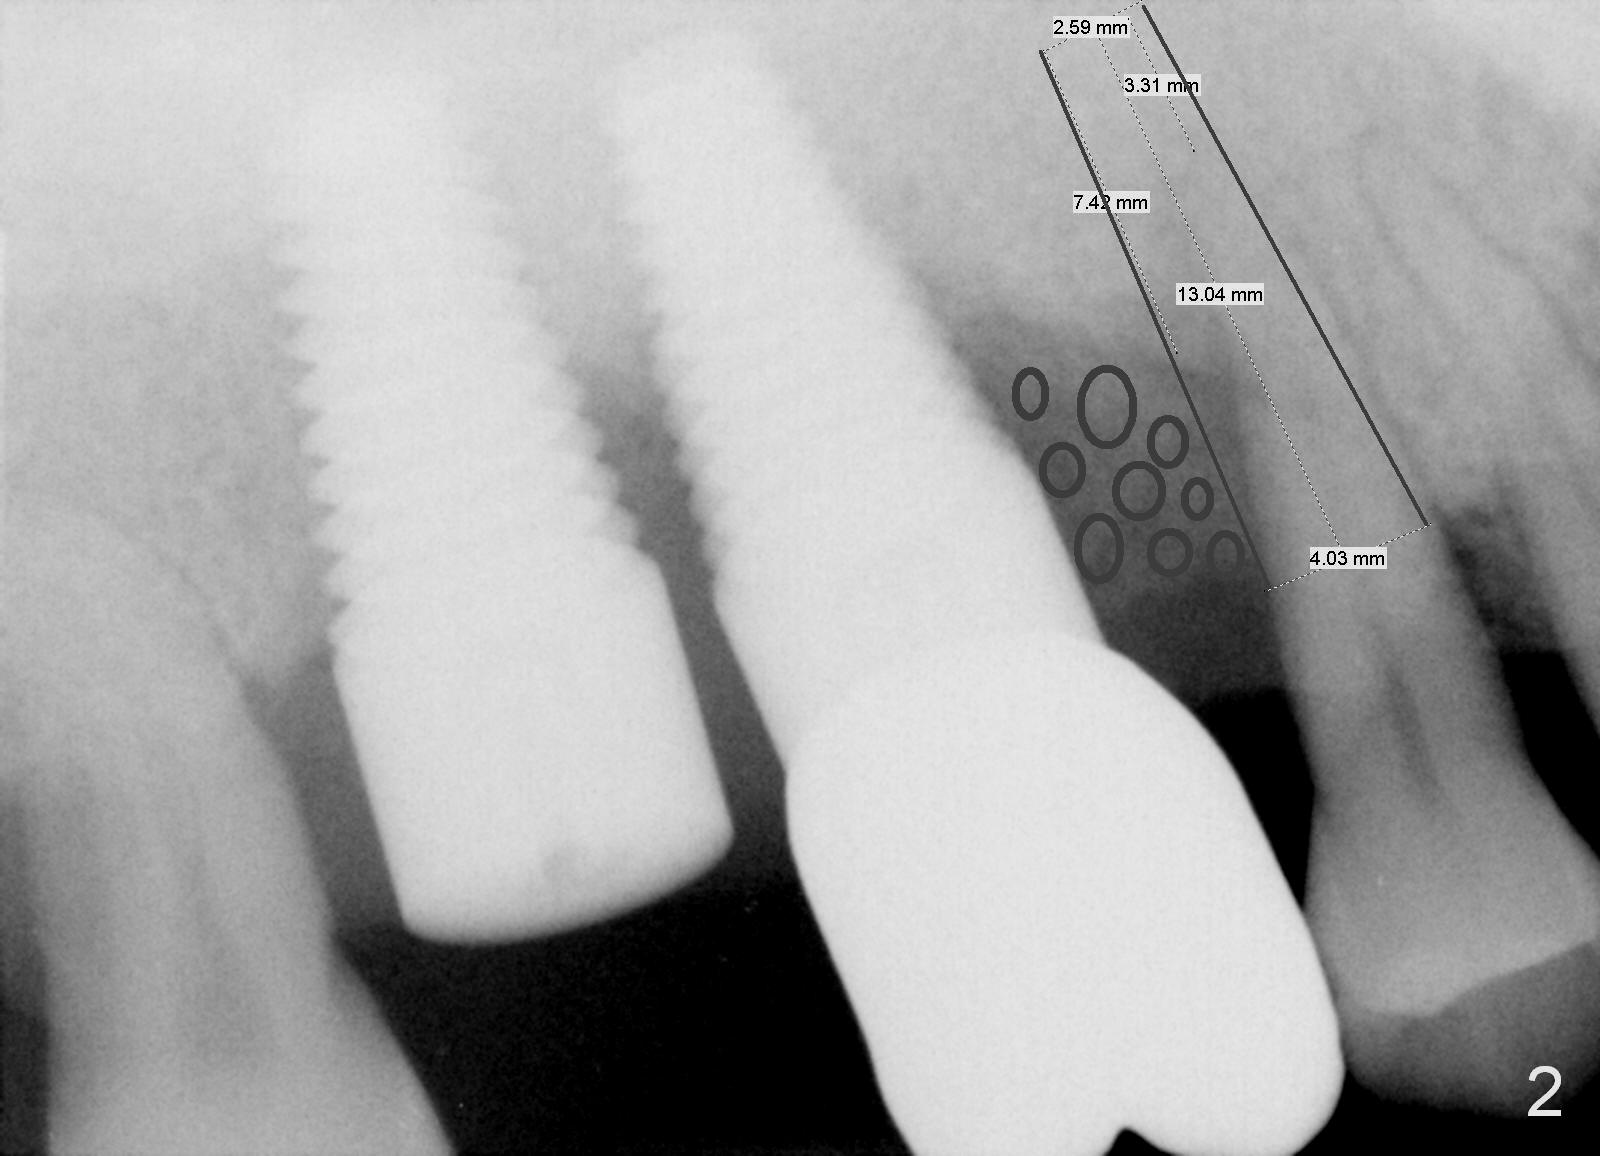

A 46-year-old man has severe chronic periodontitis associated with bruxism.  The teeth #3 and 2 have been replaced with immediate implants (Fig.1,2).  Now the tooth 4 should be treated in the same manner.  Since there is sufficient bone with uneven bone resorption, a long bone-level implant is needed for primary stability (>13 mm).  Cuff length of the tissue-level implant is fixed, while there are different lengths of the cuff associated with bone-level implants.  Metronidazole is the antibiotic to be used for socket disinfection.  Intraop PA should be taken with the pilot drill or a parallel pin to avoid invading the neighboring root or implant.  Abundant bone graft is required (circles, Fig.2).